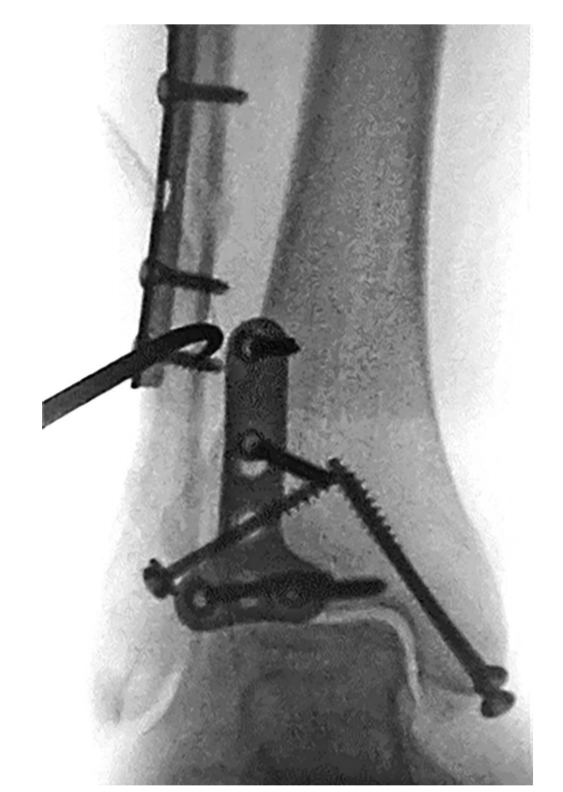

⑧ 复位后典型病例示意图。